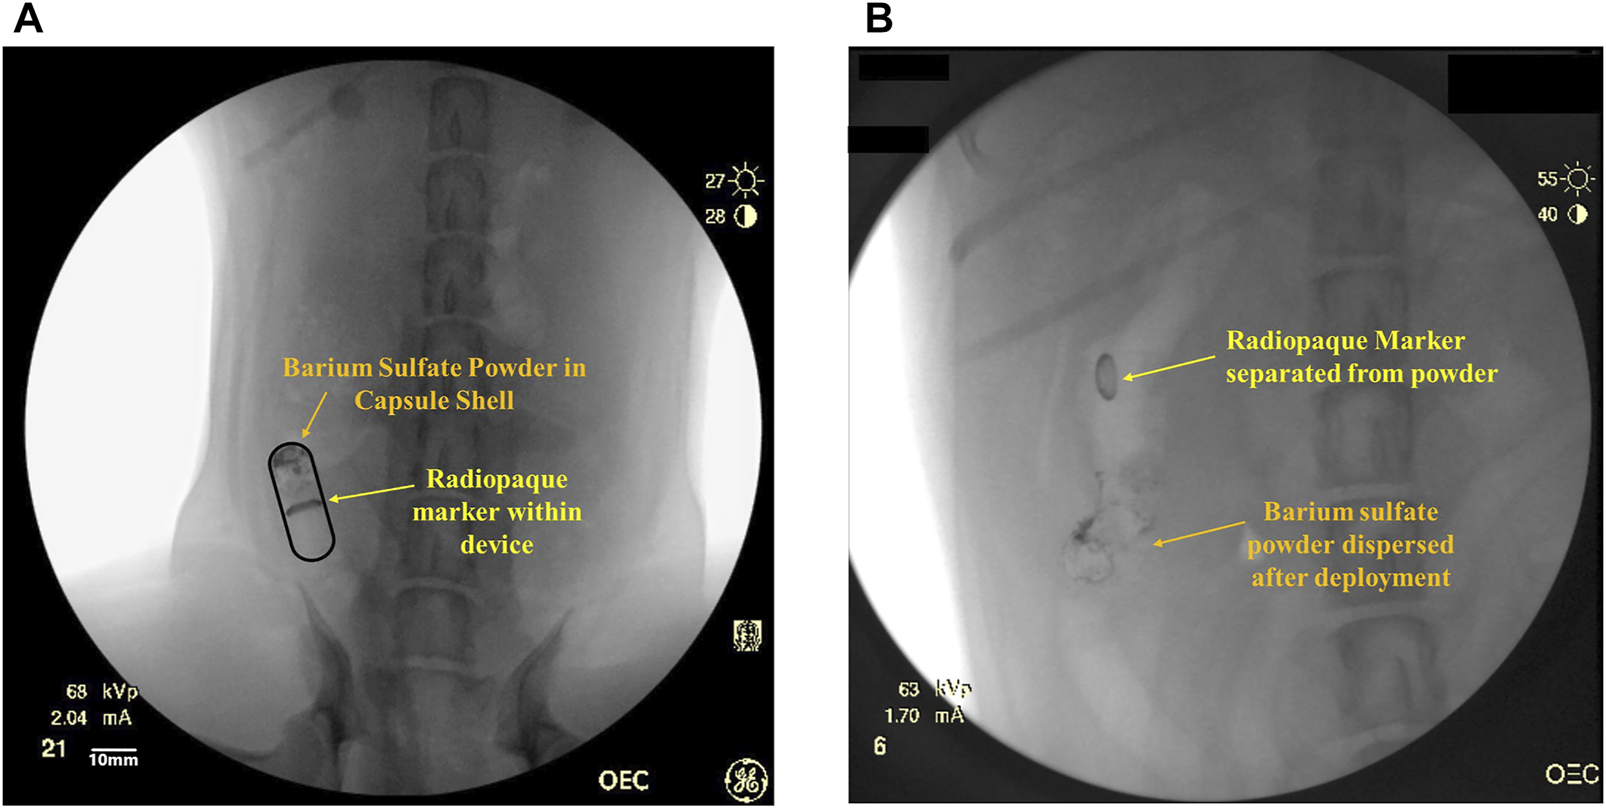

The RP contains two radiopaque markers: barium sulfate powder (Sigma-Aldrich) and a ring of bismuth (manufactured in house), which are used for tracking the transit and deployment of the RP within the GI tract using fluoroscopic imaging (Figure 1A). The barium sulfate powder is compacted in one end of the capsule shell. When the capsule shell dissolves, barium sulfate disperses indicating device deployment and drug delivery (Figure 1B) which is taken as T = 0 (± 5 min) for PK sampling. The second marker, a ring of bismuth is placed at the base of the microsyringe and stays within the balloon. The bismuth can be tracked through the GI tract to confirm the excretion of the device remnants.

FIGURE 1. (A) Representative fluoroscopic image of an intact RP within the small intestine with a radiopaque marker (bismuth) in the device and barium sulfate powder within the capsule shell. (B) Representative fluoroscopic image of deployed RP in the small intestine. The barium sulfate in the capsule has dispersed inside the intestinal lumen and has been pushed away from the radiopaque bismuth marker within the device.